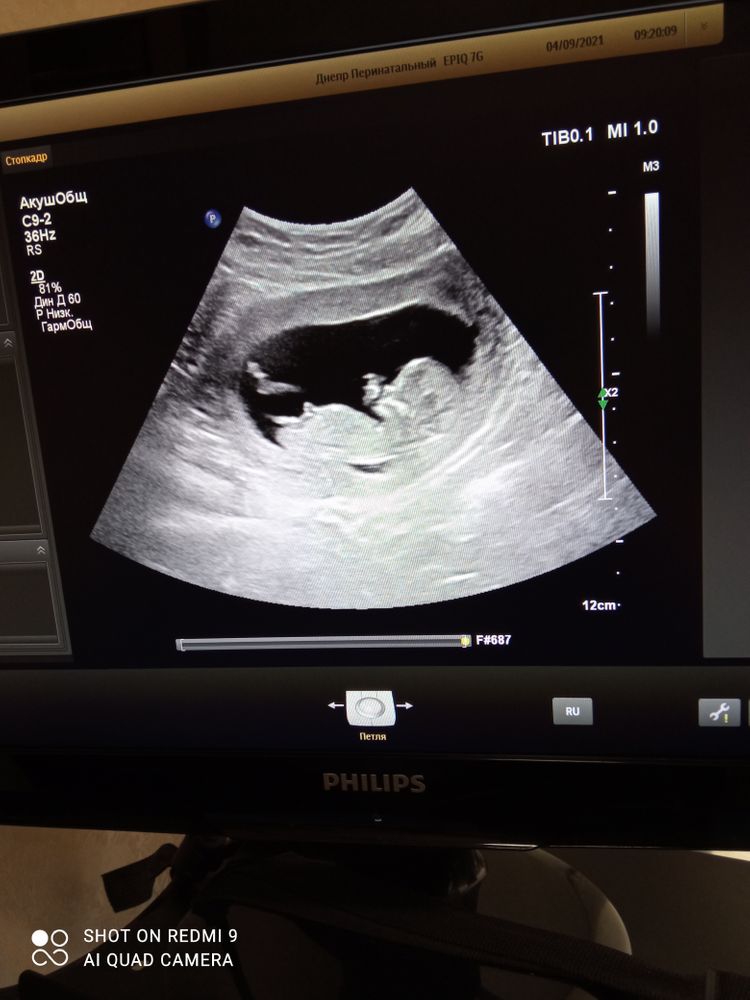

Первый скрининг, знатоки кто в домике?)

Изображение мальчик

По профилю сказала бы, что мальчик. Но это гадание на ромашке

Мальчик)

Мальчик